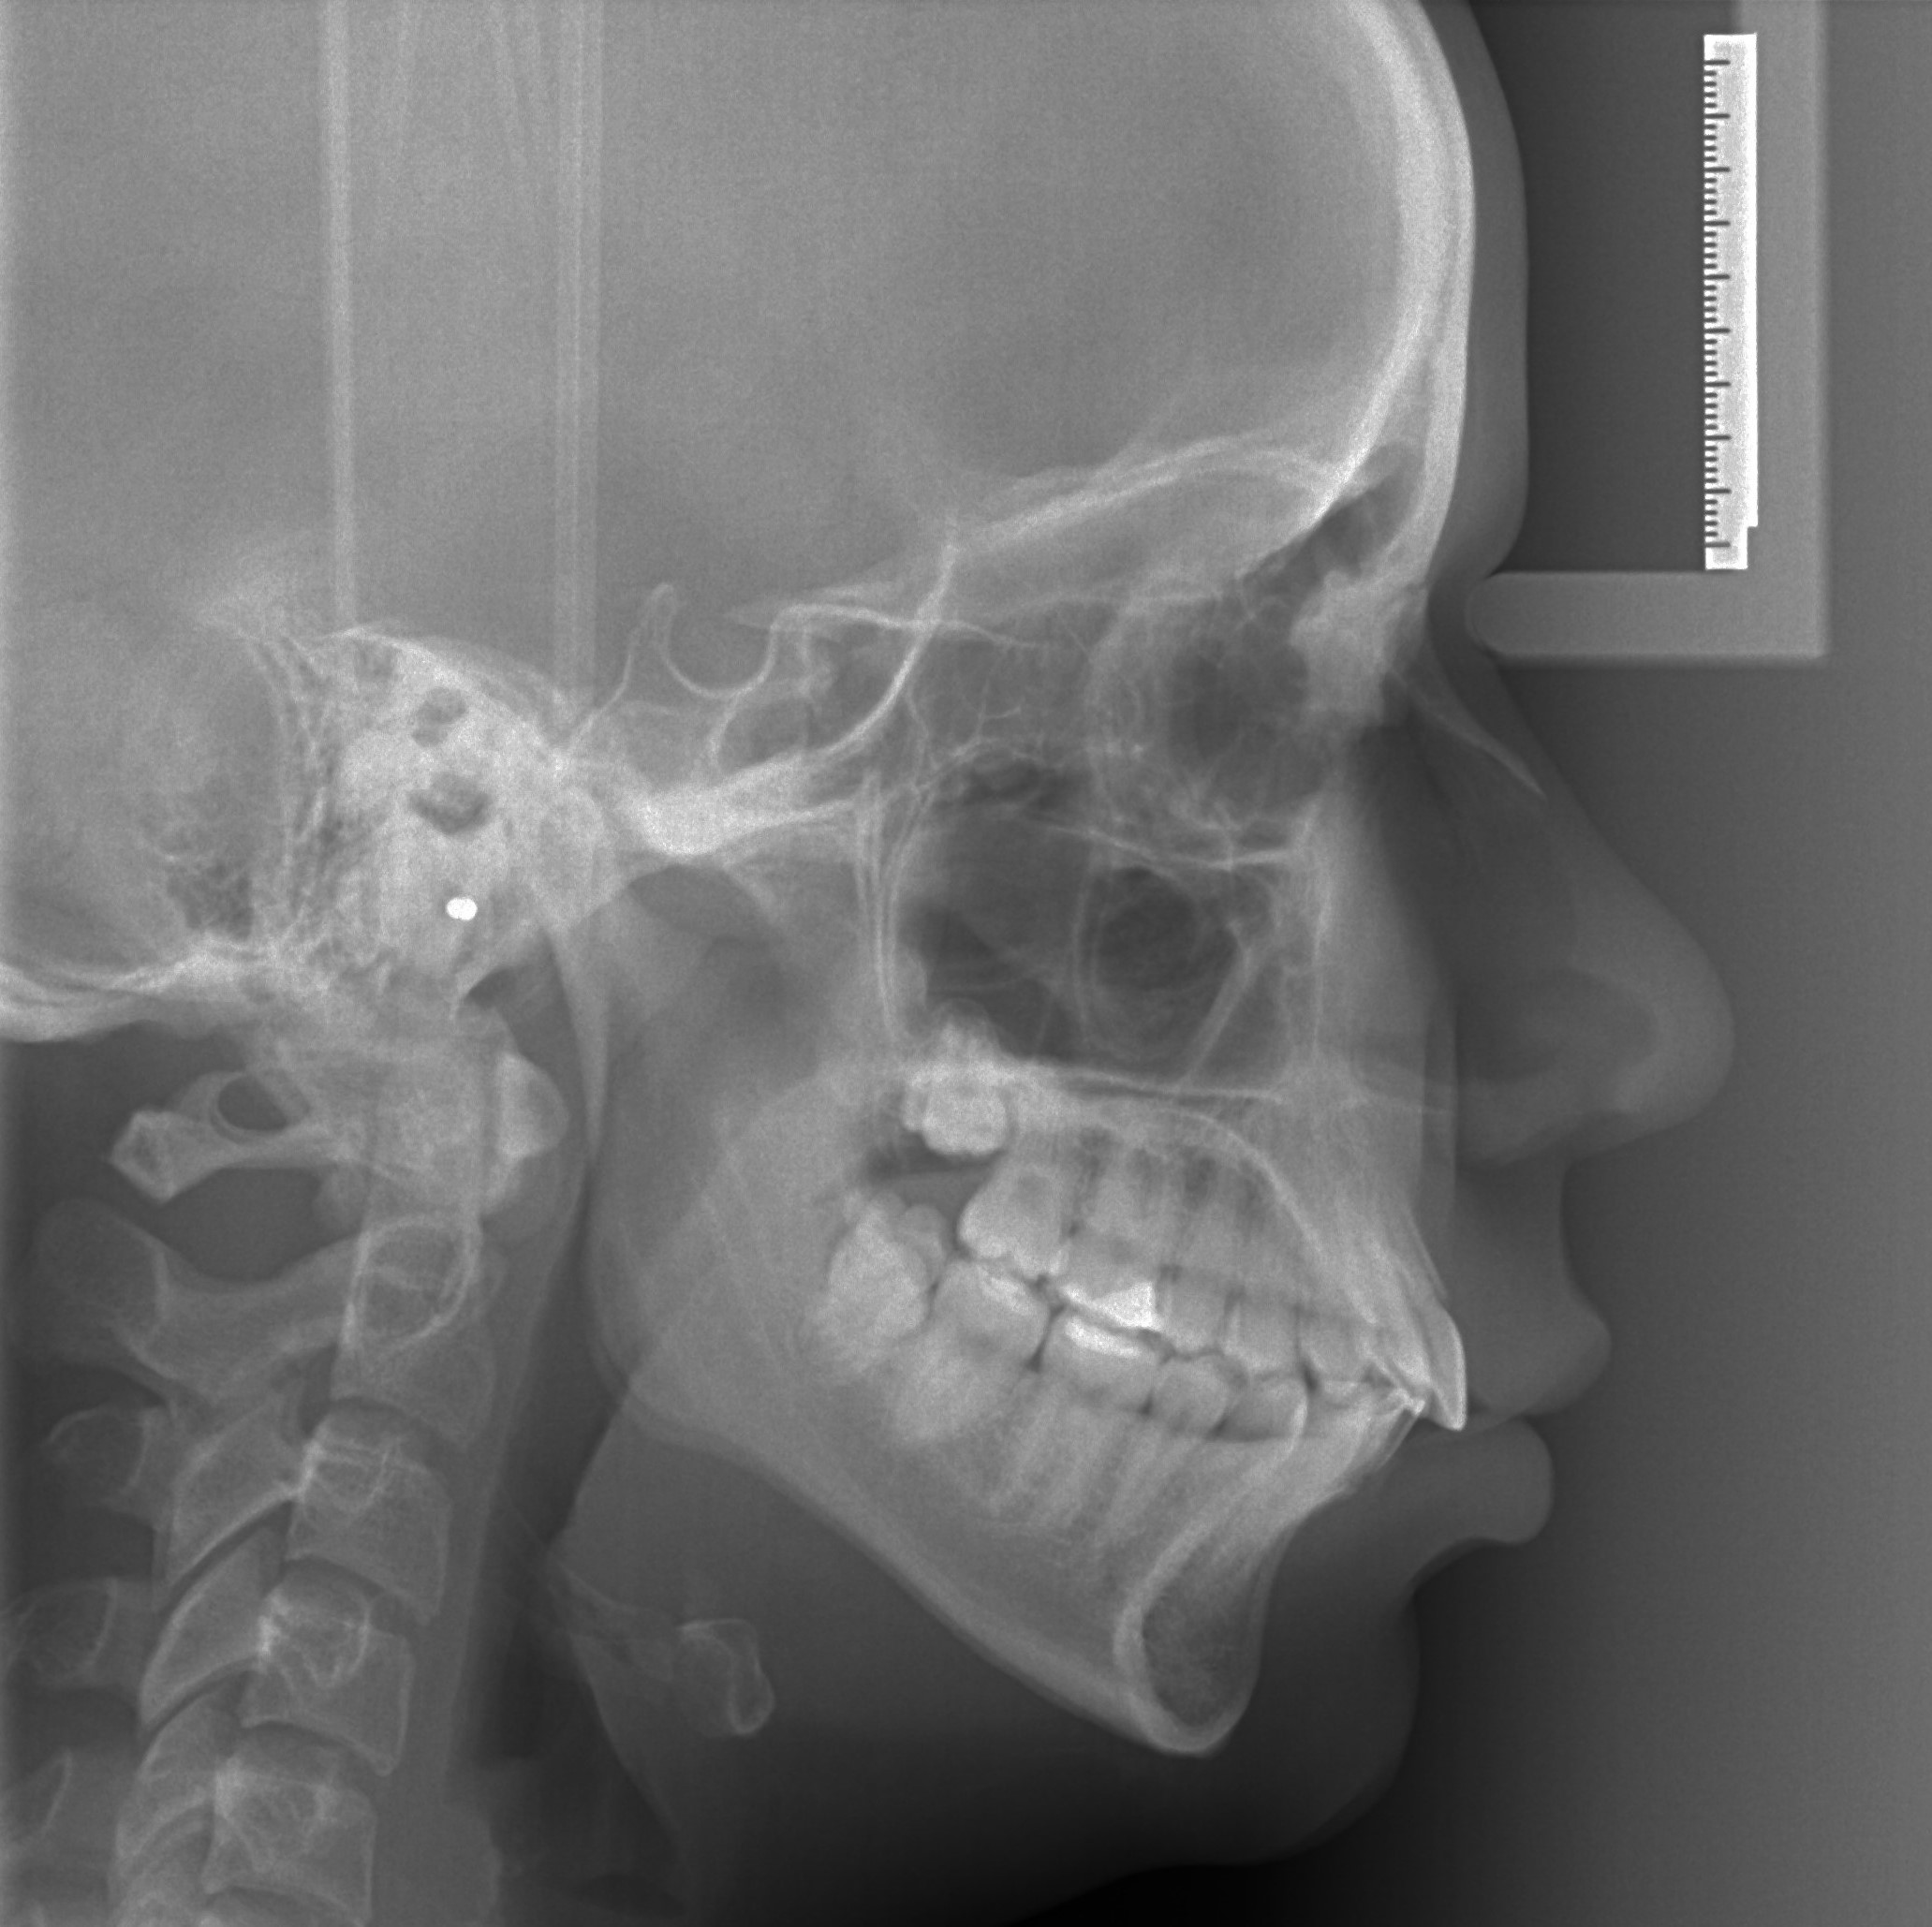

telerendgen - profilni snimak glave

Telerendgen – profilni snimak glave je specijalni snimak glave koji se najčešće koristi u ortodonciji za analizu odnosa vilica, zuba i kostiju lica. Omogućava precizno planiranje ortodontske terapije i praćenj promena prilikom lečenja.

4 000,00 rsd